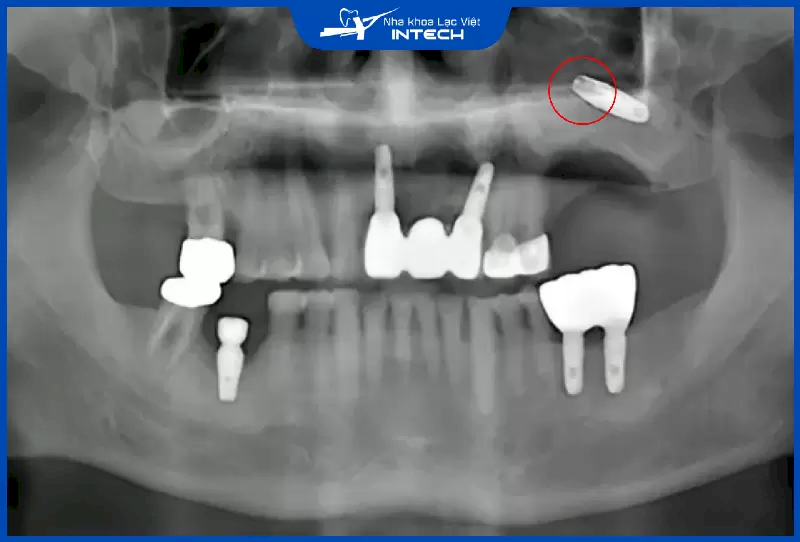

Cắm Implant bị tiêu xương là tình trạng giảm số lượng xương ổ răng và xương quanh chân răng, khiến gương mặt bị lệch, khớp cắn không chuẩn và khó khăn trong việc đặt trụ Implant, khiến răng Implant dễ bị đào thải. Bài viết này sẽ giải đáp thắc mắc của cô chú/anh chị về phương pháp điều trị tiêu xương cũng như những lưu ý về tình trạng này khi phục hình răng.